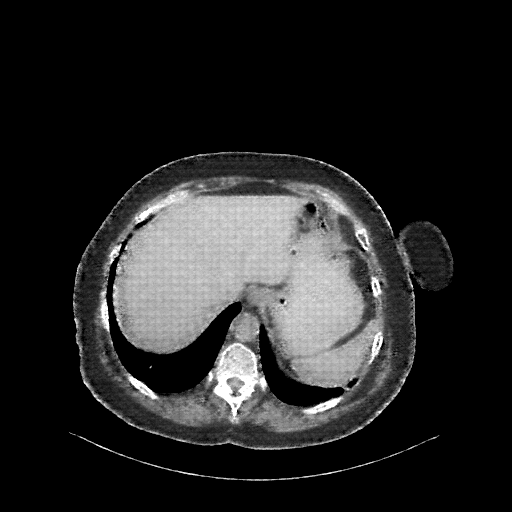

Original VENOUS CT scan

No window - Raw intensity values

Lung window (WL -600, WW 1500 β†’ Low βˆ’1350, High +150)

Mediastinum window (WL 40, WW 400 β†’ Low βˆ’160, High +240)